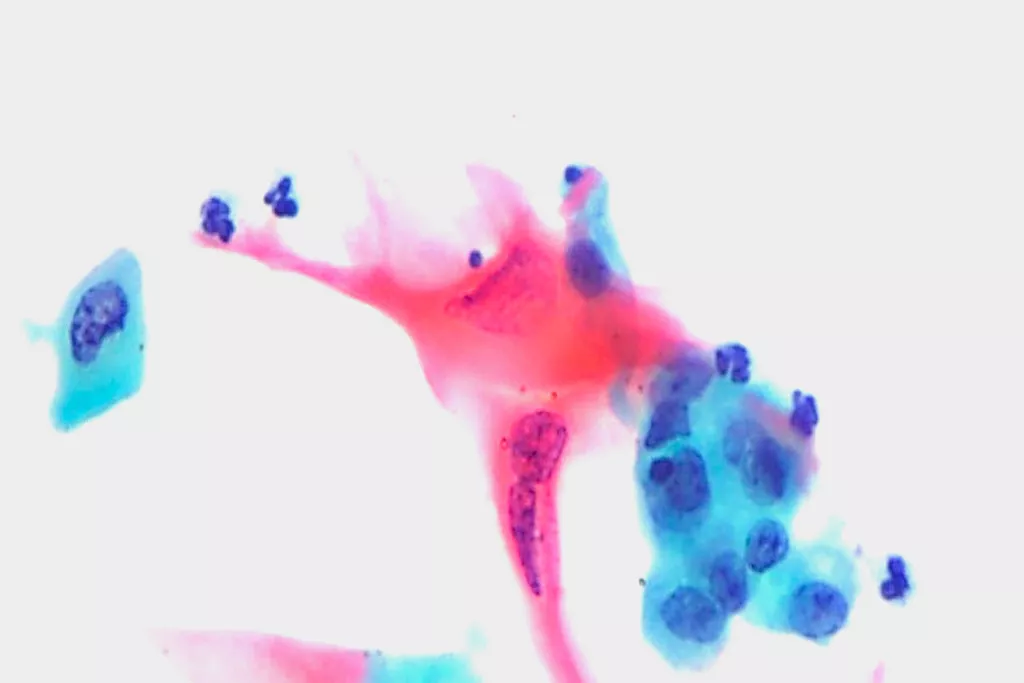

Bildgalleri9

9. Bilder från cytopatologiavdelningen, Llandough Hospital, Wales, Storbritannien